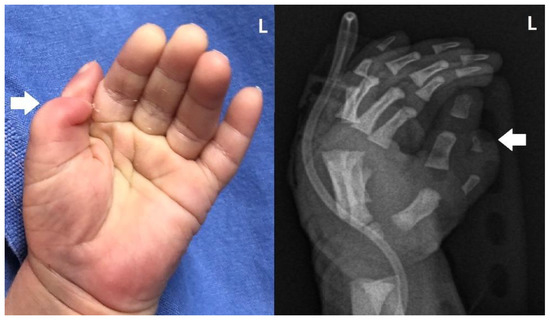

2. Detailed Case Description